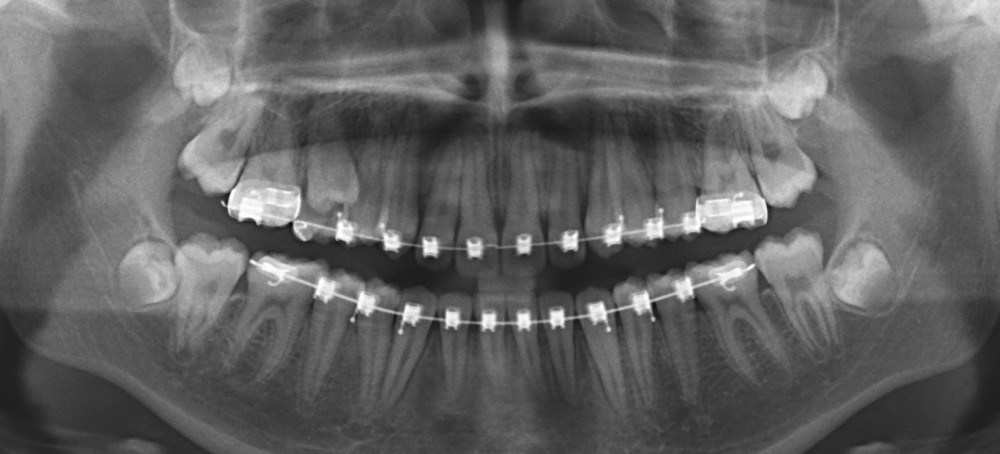

Sur la radiographie panoramique, on observe une transposition des canines maxillaires en place d’incisives latérales, au contact des racines de 11 et 21.

À ce stade, une radiographie panoramique est réalisée pour s’assurer de l’intégrité des racines, contrôler les axes dentaires et planifier le repositionnement de certaines attaches ainsi que le collage des tubes sur les secondes molaires en cours d’éruption.